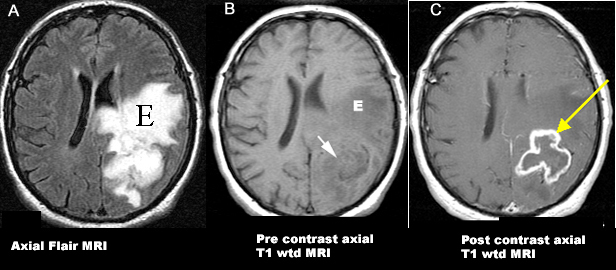

Glioblastoma / Grade IV Astrocytoma (WHO Classification).

An irregular enhancing ring lesion (arrows in B and C) is seen involving the left parietal lobe.

Tumor is associated with edema (E) best noticed on FLAIR image.

• Imaging Features: Tumor with irregular peripheral enhancement with central necrosis. t